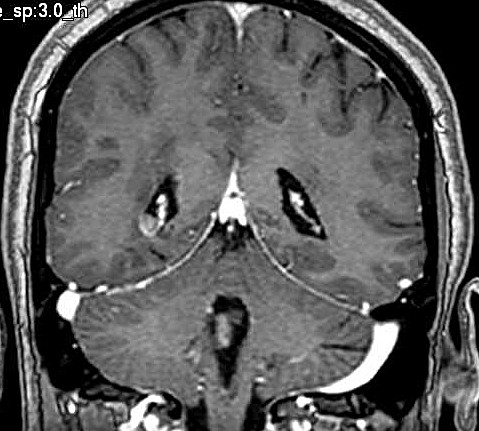

| Fem. 17a. |

| Nódulo sólido homogêneo preenchendo o III ventrículo, com limites precisos, com hipossinal em T1 e hipersinal em T2 e FLAIR, que se impregna por contraste paramagnético. Lesão menor implantada no assoalho do IV ventrículo provavelmente representa disseminação por via liquórica. |

| F. 17a. Tumor teratóide rabdóide atípico de III ventrículo. RM | HE | VIM, GFAP | HHF35, desmina, 1A4 | AE1AE3, EMA |